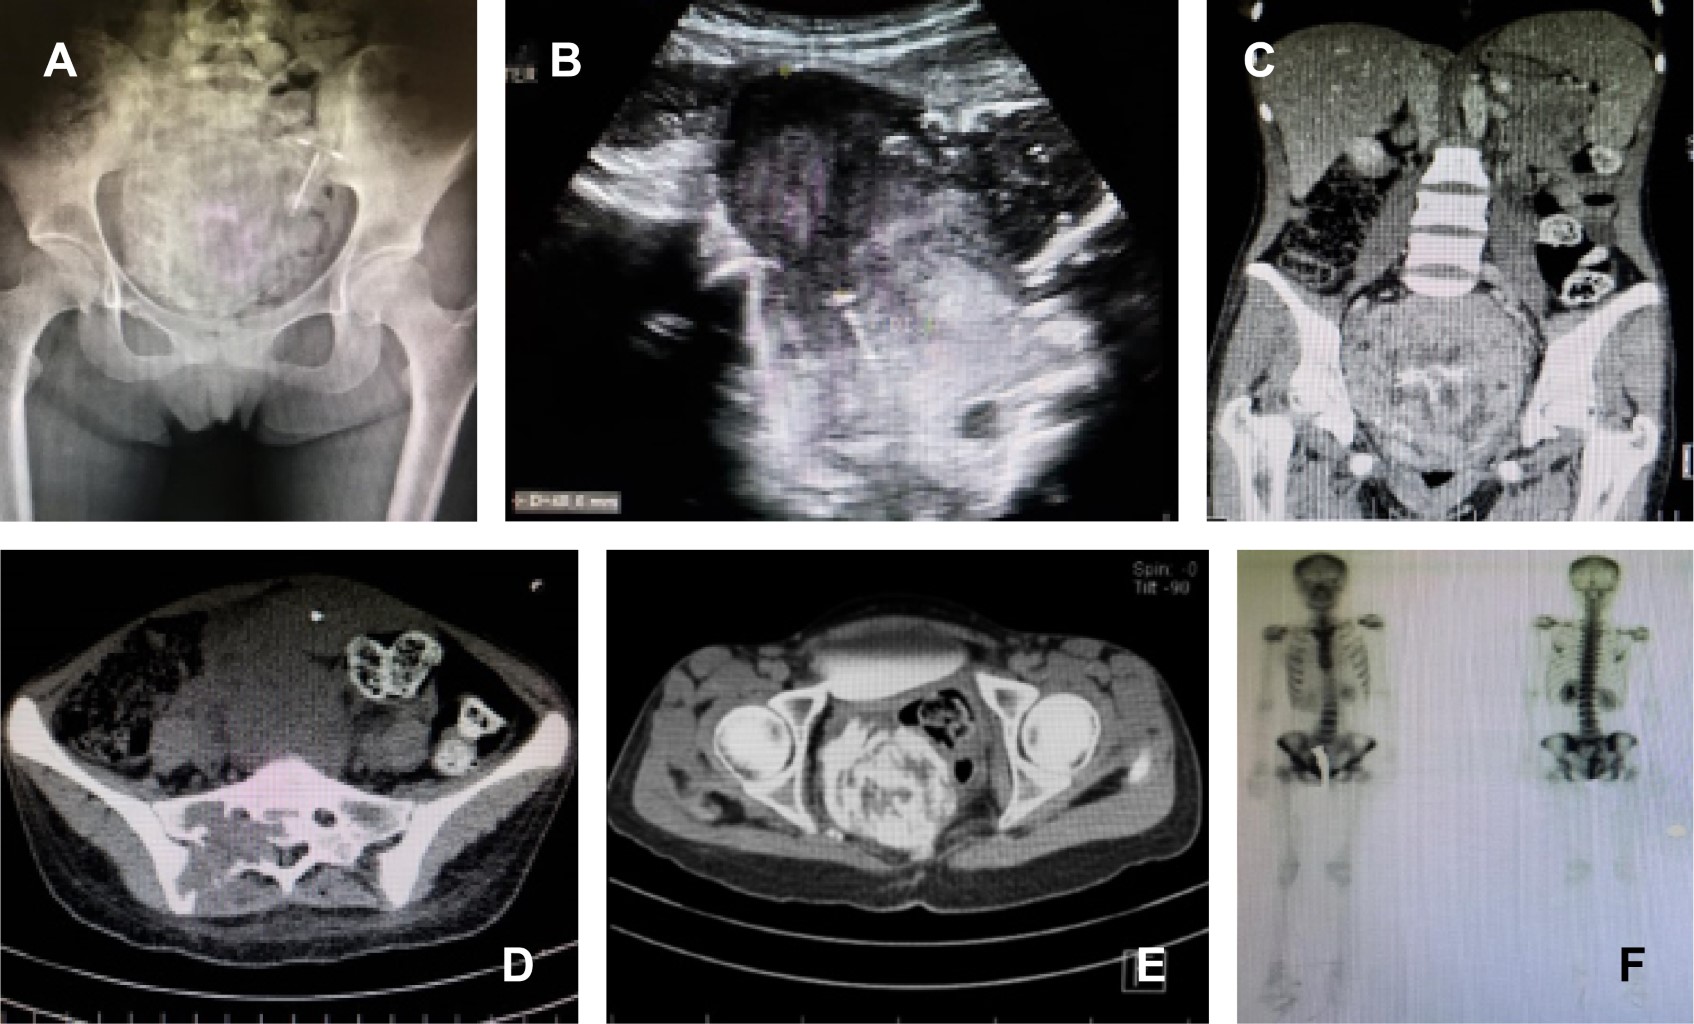

Paciente femenino de 21 años, sin antecedentes heredofamiliares de importancia; menarca a los 12 años, eumenorréica, inicio de vida sexual activa (IVSA) 18 años, parto 1, para 1. Referida al servicio de ortopedia por presentar, en un lapso de tres meses, pérdida progresiva de control de esfínteres, retención urinaria, incapacidad para la marcha, dolor y distensión abdominal. Se realizó ultrasonido abdominopélvico, el cual reveló masa tumoral intrapélvica. Se completaron estudios de tomografía computarizada y gammagrama óseo con 99mTc-MDP (Figura 1) y se efectuó biopsia de sacro, el reporte histopatológico confirmó tumor de células gigantes (TCG) de dicho hueso. Se inició tratamiento utilizando denosumab 60 mg/mes, completando ocho dosis. La evolución fue hacia la mejoría clínica, con desaparición de dolencia y parestesias, recuperación del dominio de esfínteres y marcha con ayuda de andador, el estudio de imagen de control mostró reducción de tamaño tumoral, de inicialmente 452 mm, a 98.7 mm (Figura 2).

Figura 1